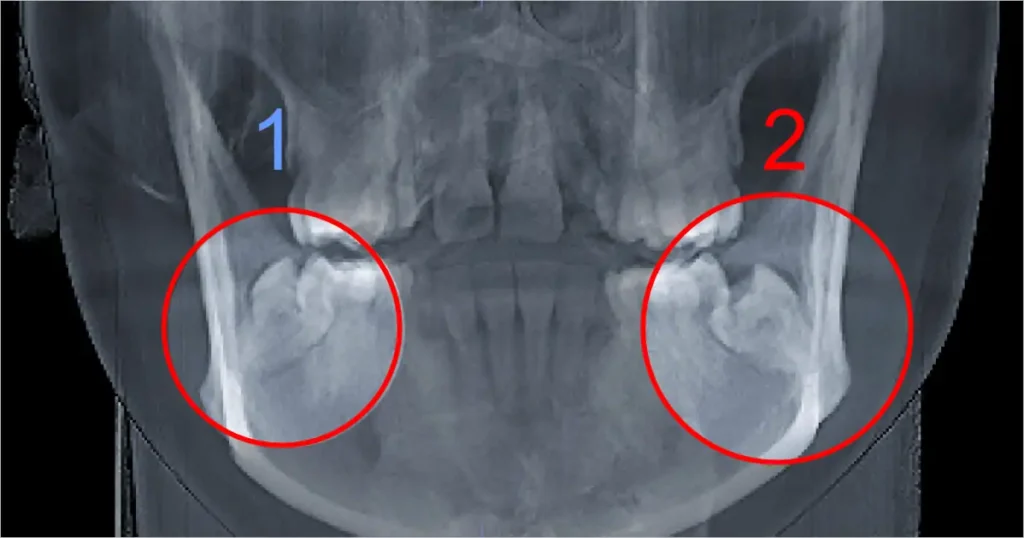

En algunos pacientes, el dolor no nace desde una caries profunda ni desde una fractura, sino desde una muela del juicio inferior que no ha terminado de erupcionar bien. Cuando parte de la corona queda cubierta por encía, esa zona puede inflamarse, retener restos y generar dolor localizado, dificultad para masticar, mal sabor, inflamación e incluso irradiación hacia el oído del mismo lado.

A este cuadro se le llama pericoronaritis. No siempre empieza como una urgencia dramática, pero puede pasar rápidamente de una molestia localizada a un problema inflamatorio o infeccioso más serio. Por eso, cuando un tercer molar parcialmente erupcionado duele, se inflama o se vuelve repetidamente sensible, lo correcto no es solo “aguantar” o automedicarse, sino evaluar la posición del diente, el estado de los tejidos vecinos y si corresponde control, manejo local o extracción.